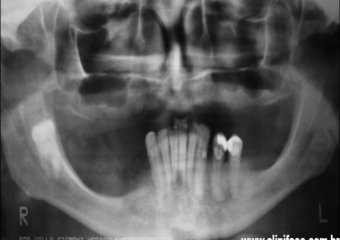

Raio X final